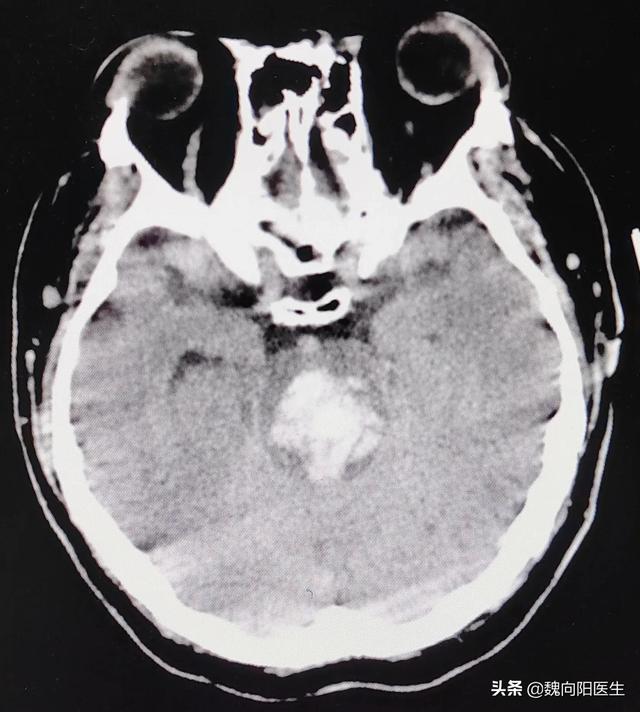

脑干出血能恢复到什么程度?(脑干出血后)

40多岁的他,因为长期没有有效控制血压,且对高血压的认识不足,并没有正规的服用降压药,最终在去年的某一天,因为脑干出血而住进了医院的重症监护室。自从发病的那一天就一直处于昏迷状态,发病前作为一名普通的工人,默默无闻地...